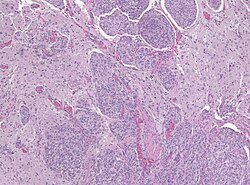

Template:Px Meningioma. HPS stain. | |

| LM | whorled appearance, calcification - psammomatous, +/-nuclear pseudoinclusions |

Microscopic

Features (memory device WCN):

- Whorled appearance - key feature.

- Calcification, psammomatous (target-like appearance; (tight) onion skin).

- +/-Nuclear pseudoinclusions - focal nuclear clearing with a sharp interface to unremarkable chromatin.

- Meningioma high mag.jpg

Meningioma - high mag. (WC)